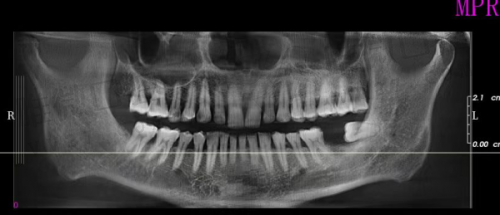

相比不少小型牙科诊所,佛山登特口腔在技术设备上的投入可一点都不含糊。诊所内配置了德国、美国等进口的数字化高新科技设备,比如3D口腔扫描仪、CBCT、种植机、激光治疗仪、超声洁牙设备等等。别小看这些“黑科技”,在种植牙、正畸、根管治疗这些领域可是非常加分的,大大提升了看牙效率与舒适感。

尤其值得一提的是“数字化种植技术”,即当天种牙当天吃饭,不用东等西等,更适合上班族或者长辈急需修复口腔功能的患者。拍片、建模、手术几乎一气呵成,效率高又精细,让“看牙难、种牙慢”这些困扰一扫而空。

院内设有多个标准化临床科室,包括口腔种植、正畸、综合治疗、儿童齿科、影像诊断、消毒供应中 心等,并配备了无菌手术室和CT影像检查设备,符合国内口腔医疗标准。